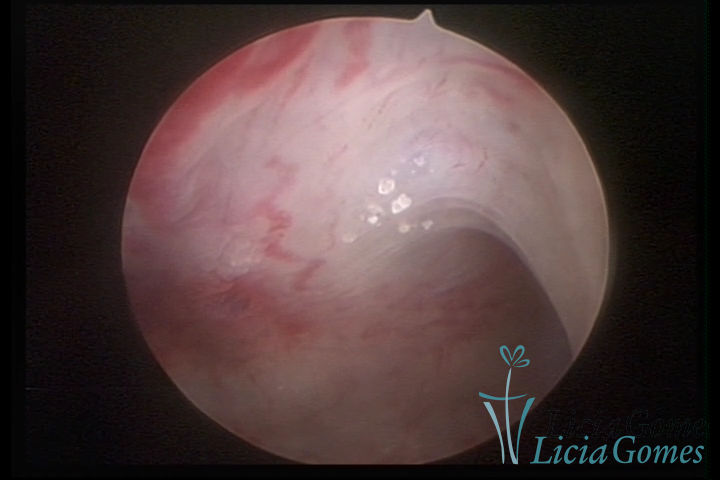

Osseous metaplasia: white spots with calcifications